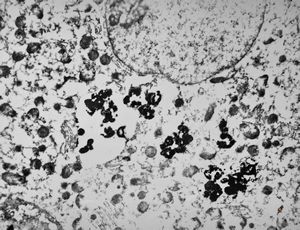

M,66y. | siderosomes

M,66y. | hemosiderin - siderosomes